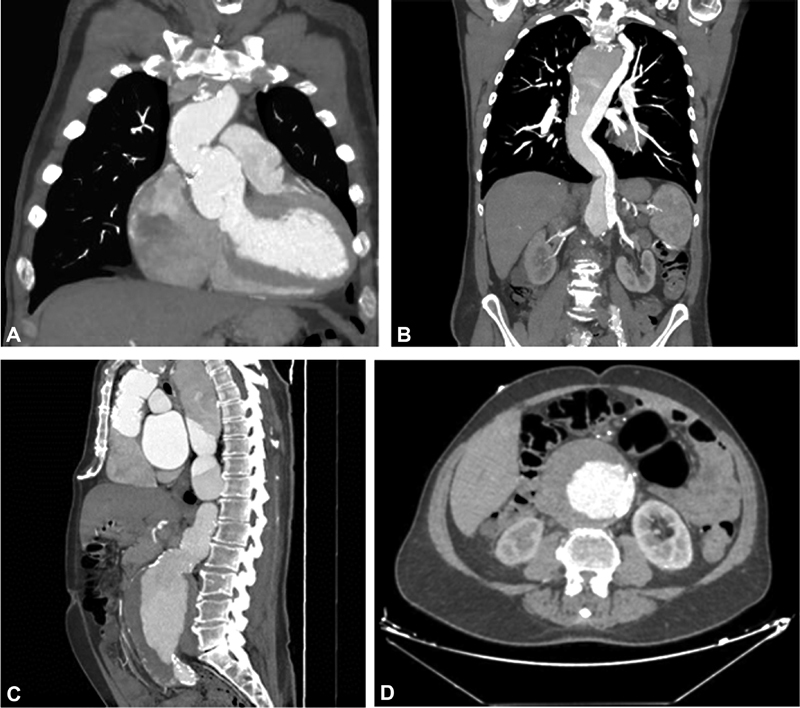

我们描述了一位66岁的男性患者的病例,他曾因急性a型主动脉夹层接受升主动脉置换术,但没有参加任何预定的随访。17年后,他因严重的主动脉反流和腹主动脉巨大的动脉瘤样扩张来到我们的机构。

We describe the case of a 66-year-old gentleman with a previous replacement of the ascending aorta for an acute Type A aortic dissection who did not attend any scheduled follow-up visit. Seventeen years later, he presented to our institution with severe aortic regurgitation and with a giant aneurysmal dilation of the abdominal aorta.